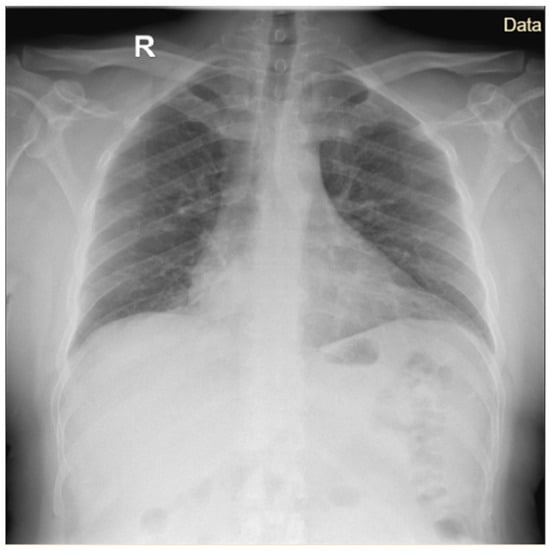

Legionnaires’ disease is a rare cause of atypical pneumonia associated with a high mortality rate among untreated patients. In Romania, the disease has historically been underreported due to insufficient surveillance and limited diagnostic capacity. The aim of this study was to describe the characteristics of Legionnaires’ disease cases admitted to a specialized infectious disease hospital between 2023 and 2024, with a particular focus on a cluster associated with travel to a spa resort. Most cases included in our study (31/36) were confirmed by urinary antigen testing, while one case was confirmed by a significant increase in the level of specific antibodies against Legionella pneumophila serogroup 1 in paired serum samples. The most frequently reported symptom was fever (28/32), followed by chills (24/32). Among the 32 confirmed cases, 3 patients died. Two cases were identified as part of a family cluster involving a father and son who had undergone physiotherapy at a balneary resort. Both patients presented with fever and gastrointestinal symptoms, and radiological investigations confirmed mixed pneumonia associated with an intense inflammatory syndrome. In the father’s case, hepatic involvement and interstitial nephritis were also identified. Early diagnosis based on epidemiological data, clinical predictive scores, and laboratory investigations would allow timely administration of targeted antibiotic therapy and may contribute to reduced mortality. Full article

Figure 1